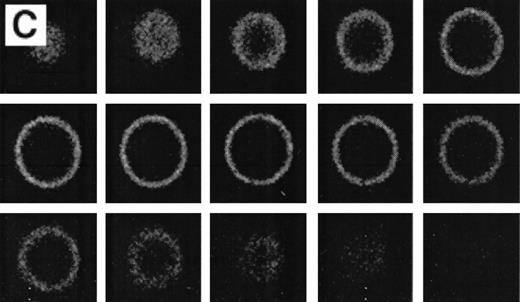

Because the number of positive cells in the thalassemic RBC samples was low, the population was enriched in AV-FITC–positive cells by magnetic bead separation as described before.15 After separation, the cells were washed with calcium-free buffer, which removed all of the AV-FITC/magnetic bead complex from the cells. These RBCs were reincubated in AV-FITC in the presence of calcium to visualize the distribution of PS on the membrane surface. These unfixed AV-FITC–labeled RBCs were then studied by CSOM, and optical sections taken at 0.5 μm cuts were made when indicated (Fig 4). When it was necessary to simultaneously analyze the distribution of PS on the red cell surface and α-globin deposits on the cytosolic site of the membrane, AV-FITC–labeled cells were lightly fixed, permeabilized, and incubated with the murine monoclonal anti–α-globin antibody, followed by Texas-Red–labeled goat antimurine immunoglobulin antibody.17 18

RBCs from a thalassemic patient (HbE/β-thalassemia, splenectomized) enriched from the population labeled with AV-FITC using magnetic beads coated with an FITC antibody (see the Materials and Methods section). (A, B) Typical cells labeled with AV-FITC in the native unfixed state and then analyzed by serial optical sections in confocal fluorescent microscopy. Panel A shows the equatorial section of a cell homogeneously labeled with AV-FITC. Panel B shows three equatorial sections of a cell heterogeneously labeled with AV-FITC. (C,D) RBCs initially labeled with AV-FITC in the unfixed state and then labeled with monoclonal anti–α-globin chain antibody, and secondary Texas-Red–labeled goat antimurine antibody. This double-labeled cell was then analyzed by fluorescent microscopy. The areas where Texas Red (red) and FITC (green) overlap are yellow.

Figure 4 shows representative fields of RBCs from a splenectomized patient with HbE/β-thalassemia PS exposing RBCs, enriched by magnetic bead separation, relabeled with AV-FITC, and analyzed by CSOM, showed two patterns of fluorescence. Approximately half of the AV-FITC–labeled thalassemic RBCs show a smooth rim fluorescence over the entire membrane (Fig 4A), similar to normal cells with a scrambled membrane (Fig 3). However, in other RBCs the AV-FITC membrane fluorescence was more heterogeneously distributed. In addition to a rim fluorescence, sites with increased fluorescence were observed, indicating that PS was enriched in these areas (Fig 4B). Interestingly, these AV-FITC–labeled sites at the surface of the cell were localized to areas that seemed to bulge over an inclusion body as shown in the equatorial cut of such labeled cells shown in Fig 4B. Because this patient had severe β-thalassemia intermedia, it was logical to suppose that the inclusion was a membrane associated deposit of excess α-globin chains, which we tried to confirm using the monoclonal antibody to denatured α-globin chains shown by Texas-Red–labeled antimurine immunoglobulin.

The equatorial cut (midsection) of such labeled cells showed the enrichment of Texas Red in distinct areas, indicating that denatured α-globin chains were localized in domains adjacent to the membrane, confirming results reported before.18 When such RBCs were analyzed for both AV-FITC (green) and anti–α-globin/Texas-Red (red), fluorescence microscopy showed a bright-yellow fluorescence in dual-color analysis, indicating that both AV-FITC and the Texas-Red label were enriched in the same membrane regions (Fig 4B and C). In contrast, the cells that labeled homogeneously with AV-FITC did not label with Texas Red. These data strongly suggest a colocalization of denatured α-globin chains and PS in the same area.